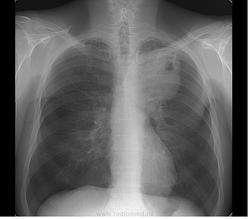

Не могу согласиться со всеми. Образование большое и, если был рак, то при таком размере контуры не должны быть такими чёткими и больше волнистыми, изменения окружающего ЛР нет. Характерное место для лимфом, но не встречал их распада. Абсцесс не надо ислючать, они уже не дают классической клинической картины. КТ, бронхоскопия, гистология.

А почему теперь абсцессы типичной клиники не дают? Мне представляется, что если бы был недренированный абсцесс такого размера, то мужчина бы себя очень плохо чувствовал, температурил и вообще помирал.... А то что контуры четкие - встречала в литературе, как некоторые авторы пытались соотнести рентгенологическую картину и гистологический тип опухоли.. так вот при каком-то виде рака указывали сохранение четких контуров образования даже при больших размерах

+1, однозначно- связь с плеврой, полость распада

Периферический с распадом.

Постараюсь отследить судьбу пациента. На данный момент его направили с заключением абсцесс верхней доли в стационар.

Верхний контур не такой уж четкий и ровный, тяжи к плевре.. внутренние контуры "полости" тоже.

Периферический, доросший до центрального с распадом.

все таки полость не такая щелевидный краевой распад.

Написано T4 N1 M1b NSCLC adenocarcinoma of lung